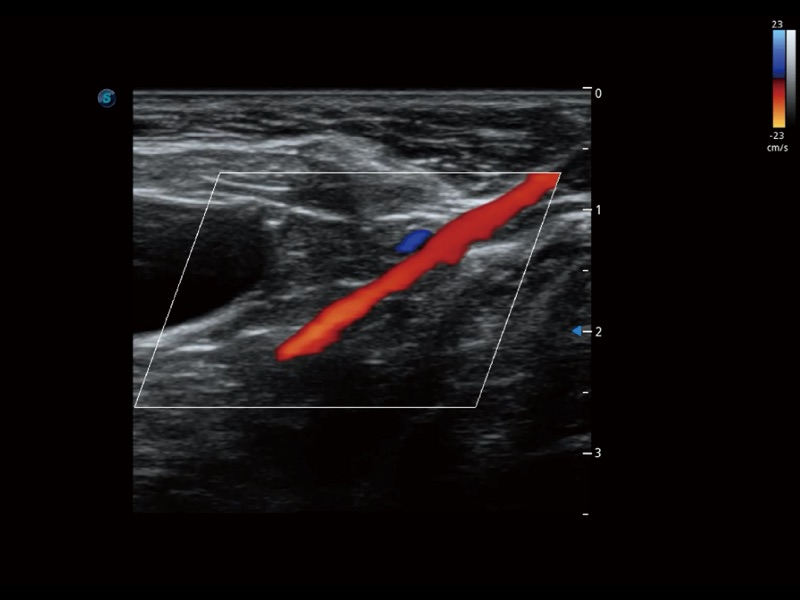

通过创新的 Matrix E自适应滤波器和超长时间域算法,极大提升超低速微细血流的检出能力,同时更精准地滤除软组织和噪声信号,为兽用医生提供以往无法通过常规血流获得的疾病诊断信息。

通过色彩血流和实时宽景相结合,可观察到完整的静脉或动脉的血流,方便医生检查。实时扫查过程中,如有任何操作失误也可以很容易地进行回扫擦除,而不会中断扫查。

ProPet 70 全新的动物超声智能软件和丰富的探头群,为动物医生提供了高清晰度和精细分辨率的图像,无论在宠物、马科、畜牧还是实验室动物等应用中都可以轻松应对,为您的日常工作带来满意的体验。